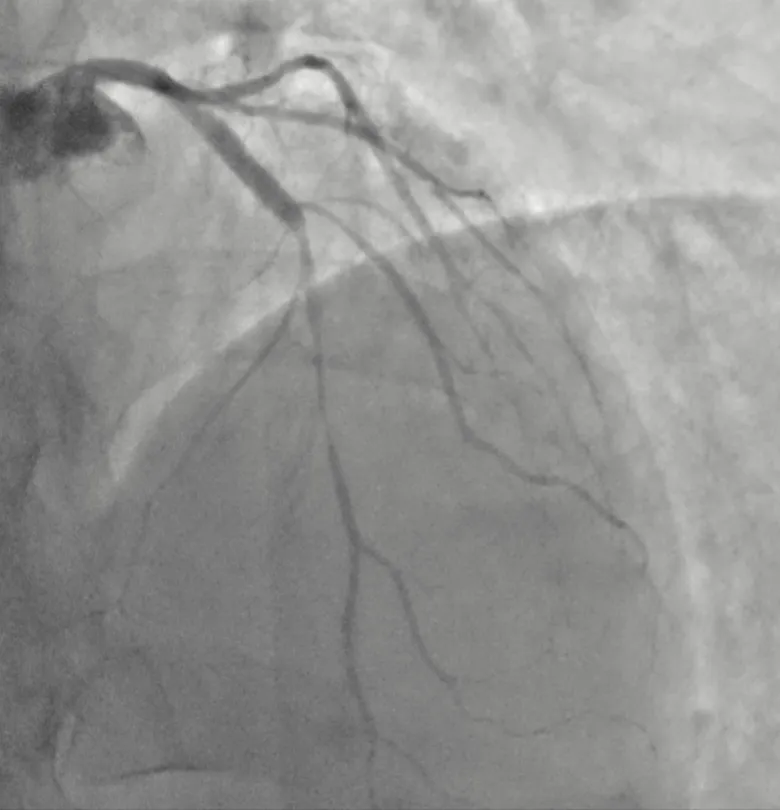

试验过程严谨有序:在持续心电、血压监测下,医生经导管向左冠状动脉内缓慢推注麦角新碱。药物推注后约1分钟,患者立即再现了与入院时相同的胸痛,与此同时,监护心电图再次显示前壁导联ST段改变。冠脉造影实时影像清晰地显示:患者的前降支冠状动脉出现严重的弥漫性痉挛,管腔直径狭窄超过90%,几近闭塞(右冠状动脉激发试验阴性)。“罪魁祸首”在镜头下原形毕露!团队立即经冠脉注入硝酸甘油,痉挛迅速解除,血管恢复通畅,患者胸痛随之消失,心电图也恢复正常。

至此,一例典型的“变异型心绞痛”(冠状动脉痉挛所致)被明确诊断。从“无异常”到“重度痉挛”,动态的造影影像和心电图变化构成了诊断的铁证。

图:冠脉激发试验后

图:硝酸甘油200ug注射后